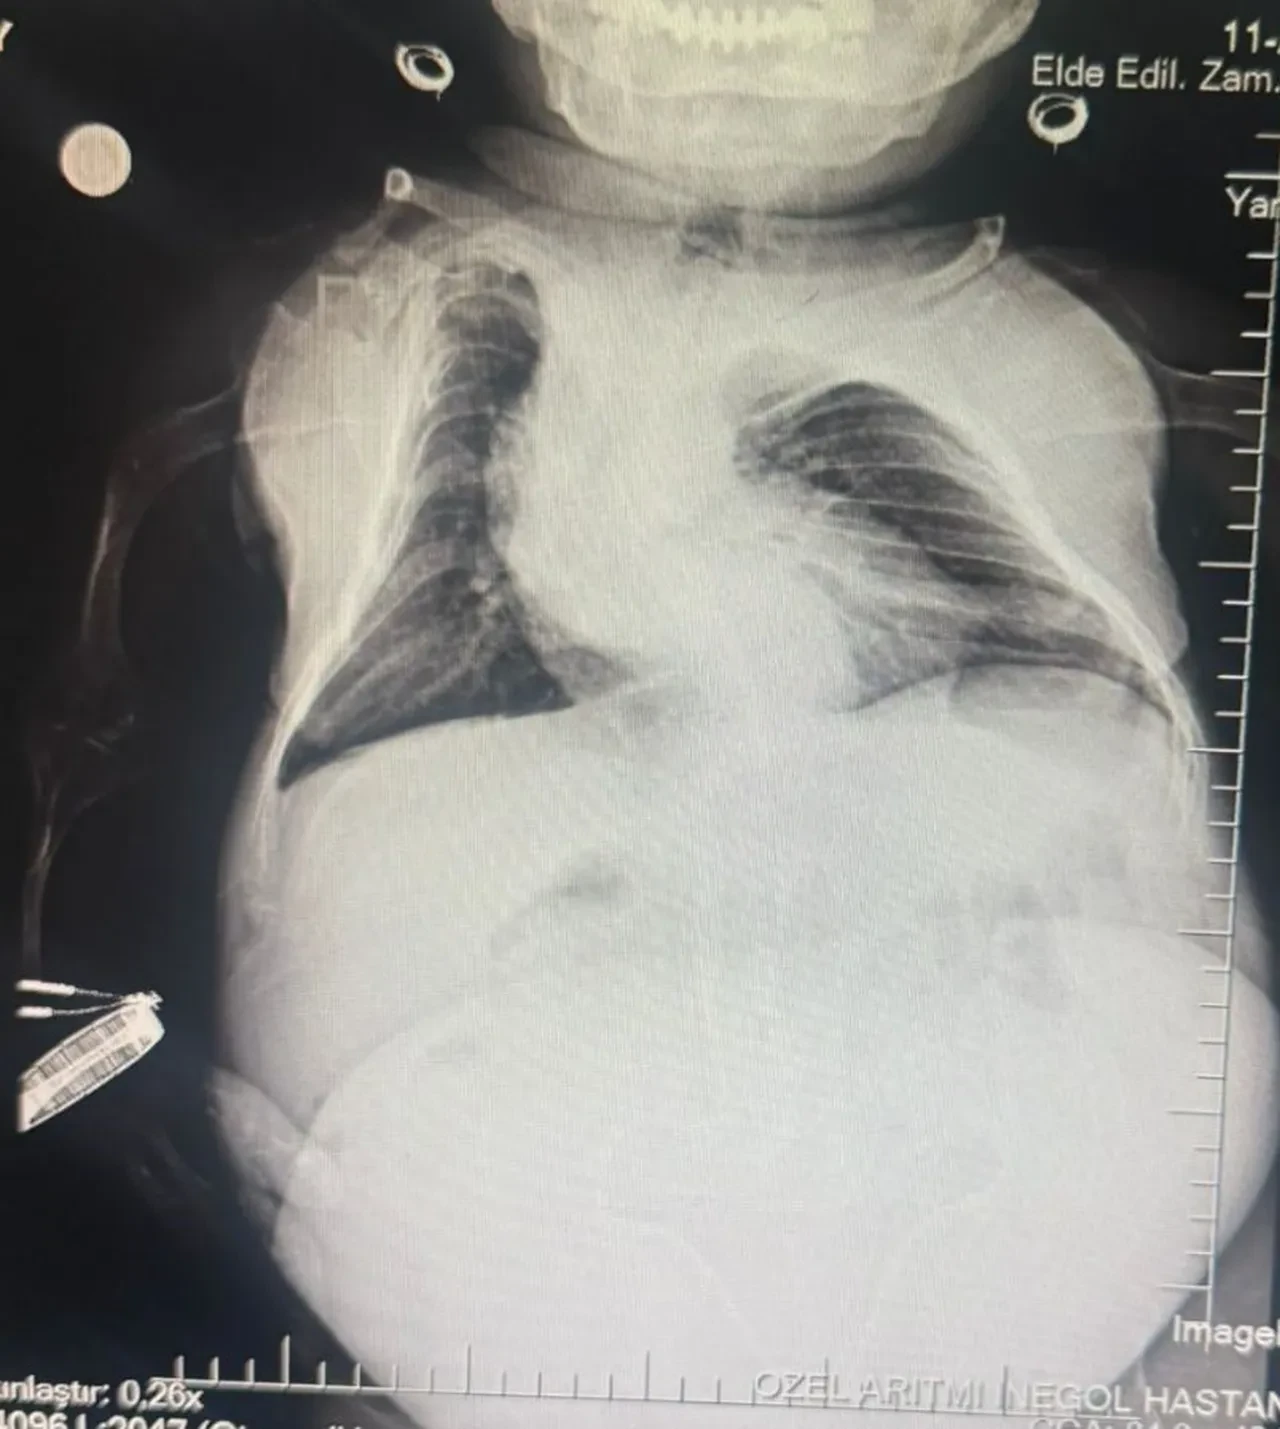

Son olarak İnegöl’deki özel bir hastanenin kadın hastalıkları bölümüne giden, 80 santimetre boyunda ve 24 kilogram ağırlığındaki Tüfekçi’nin yapılan tetkiklerinde yumurtalığında 3 kilogramlık kist belirlendi.

Hemen ameliyata alınan hasta, belinden yapılan anestezi ile uyanık şekilde gerçekleştirilen 1,5 saatlik operasyonu başarıyla atlattı. Kistten kurtulan Tüfekçi’nin kilosu 24’ten 21’e düştü.

Nurdan'ın ablası Tuğba Karakuş, "Kardeşimin ortalama 1 yıldır bu rahatsızlığı vardı. Çeşitli hastanelere gittik, acile gittik. Hep gaz problemi olduğundan bahsetmişlerdi. Sonra birde burayla görüşmek istedik. Burada sağ olsun doktor bey gerçekten çok ilgilendi. Mustafa Bey anında müdahale etmeye hazırdı ve kist olduğunu söyledi 17-18 santimetre büyüklüğünde. Sonra da Mahmut Bey ile görüştük, o da elinden geleni yapacağını söyledi ve böyle bir ameliyata karar verdik. Şu an için sağlıklı olduğunu düşünüyoruz. Teşekkür ederim" dedi.